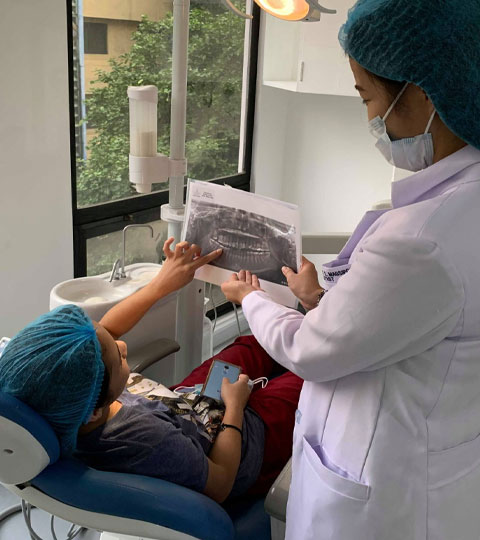

- Dental Facilities